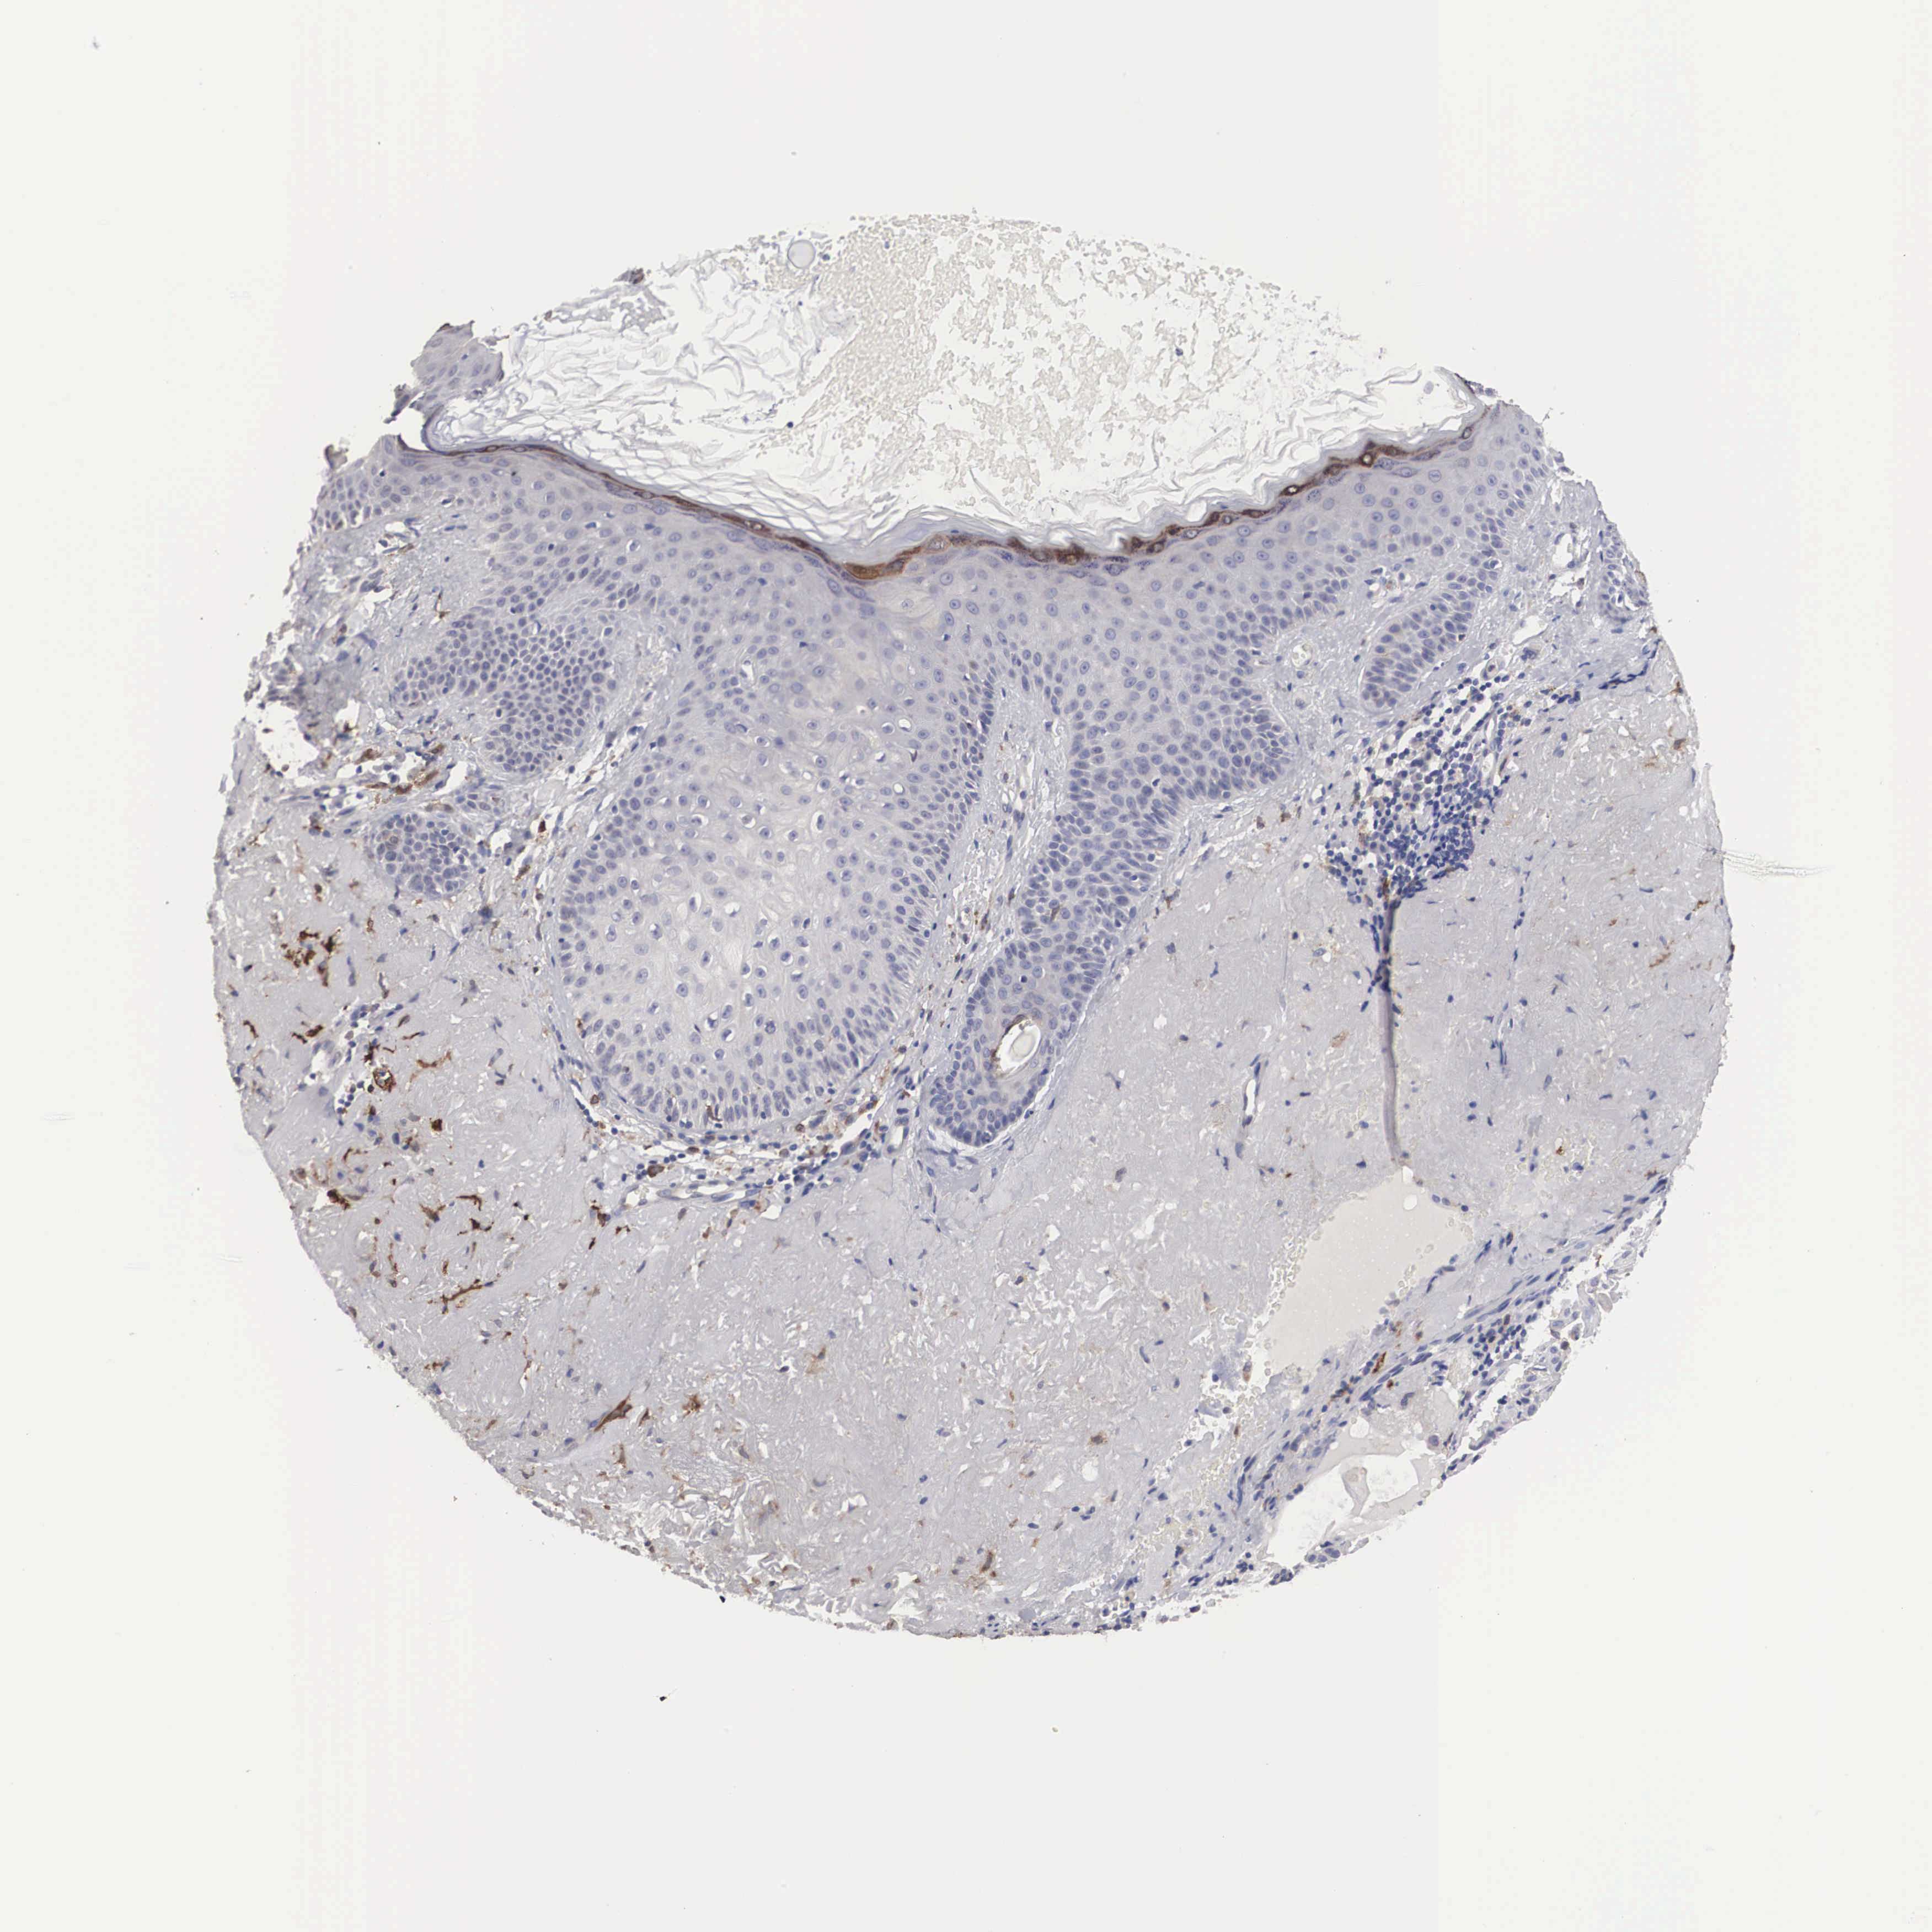

Basal cell and squamous cell cancer

SKIN CANCER - Protein expressioni

A mouse-over function shows sample information and annotation data. Click on an image to view it in a full screen mode. Samples can be filtered based on level of antibody staining by selecting one or several of the following categories: high, medium, low and not detected. The assay and annotation is described here.

Antibody stainingi

Antibody staining in the annotated cell types in the current human tissue is reported as not detected, low, medium, or high, based on conventional immunohistochemistry profiling in selected tissues. This score is based on the combination of the staining intensity and fraction of stained cells.

Each image is clickable and will lead to virtual microscopy that enables deeper exploration of all samples and also displays staining intensity scores, fraction scores and subcellular localization as well as patient and tissue information for each sample.

Antibody HPA000635

Antibody CAB017444

Basal cell carcinoma